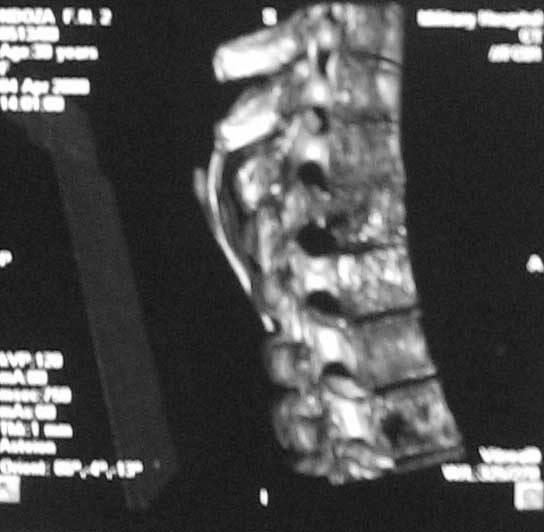

Случай действительно не стандартный и по результататам операционной ревизии обойтись без первичной иснрументации не удалось. первым этапом выполнена задняя ТПФ, вторым - левосторонняя торакотомия (соответственно максимальным изменениям паравертебральных тканей). при ревизии выявлено, что "жидкого" гноя нет, позвонки окружены гнойными вялыми, практически не кровоточащими грануляциями, тела позвонков Т5-9, включая 8 представляют собой "медовые соты ", фрагменты тел позвонков легко удаляются даже пинцетом. спинной мозг также сдавлен гнойными грануляциями. Тела Т5-9 удалены полностью. Установлен пористый никелид титана, обильно "сдобренный" цефобидом. Проточно-промывное дренирование.

spondylodiscit 6.jpg